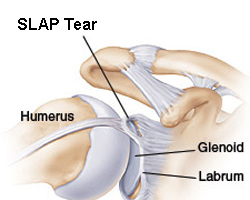

¿QUÉ ES LA LESIÓN SLAP?:

La lesión SLAP es la afección de la inserción o anclaje del tendón de la porción larga del bíceps en el hueso glenoides que forma parte de la articulación del hombro. Esto genera mucho dolor y limitación para movimientos del hombro. puede percibirse un resalto o chasquido en algunos casos.

Los desgarros pueden ser parciales o pueden ser completos, presentando dificultad o incapacidad para elevar el brazo.